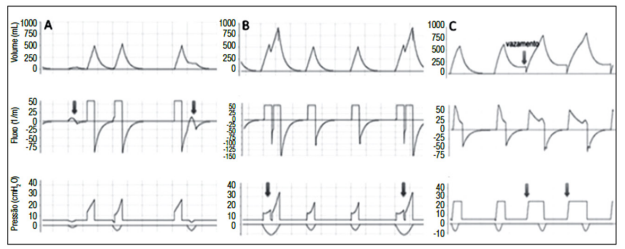

O domínio da ventilação mecânica é um dos requisitos básicos do médico intensivista. Assincronia paciente-ventilador é a incoordenação entre os esforços e as necessidades ventilatórias do paciente em relação ao que é ofertado pelo ventilador. São eventos frequentes, presentes em 10% a 80% de todos os ciclos e que se associam a prolongamento da ventilação mecânica e da internação na unidade de terapia intensiva. Sobre o assunto e a seguinte figura, assinale a alternativa correta. enunciado 1256697-1